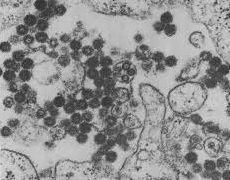

ウマ(馬)の病気  ウイルス

ウイルス  ウイルス

ウイルス  家禽用の飼料添加物